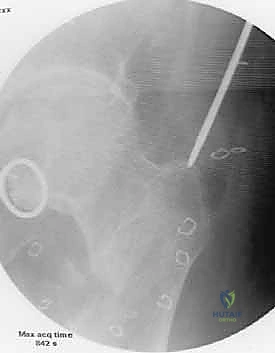

إعادة بناء العظم بين المفصلين بالطعوم أو الأطراف الصناعية: حلول متقدمة لأورام العظام في اليمن

اكتشف جراحة إعادة بناء العظم بين المفصلين لعلاج أورام العظام وإنقاذ الأطراف من البتر باليمن مع د. محمد هطيف. تقنيات متطورة تحافظ على المفاص…